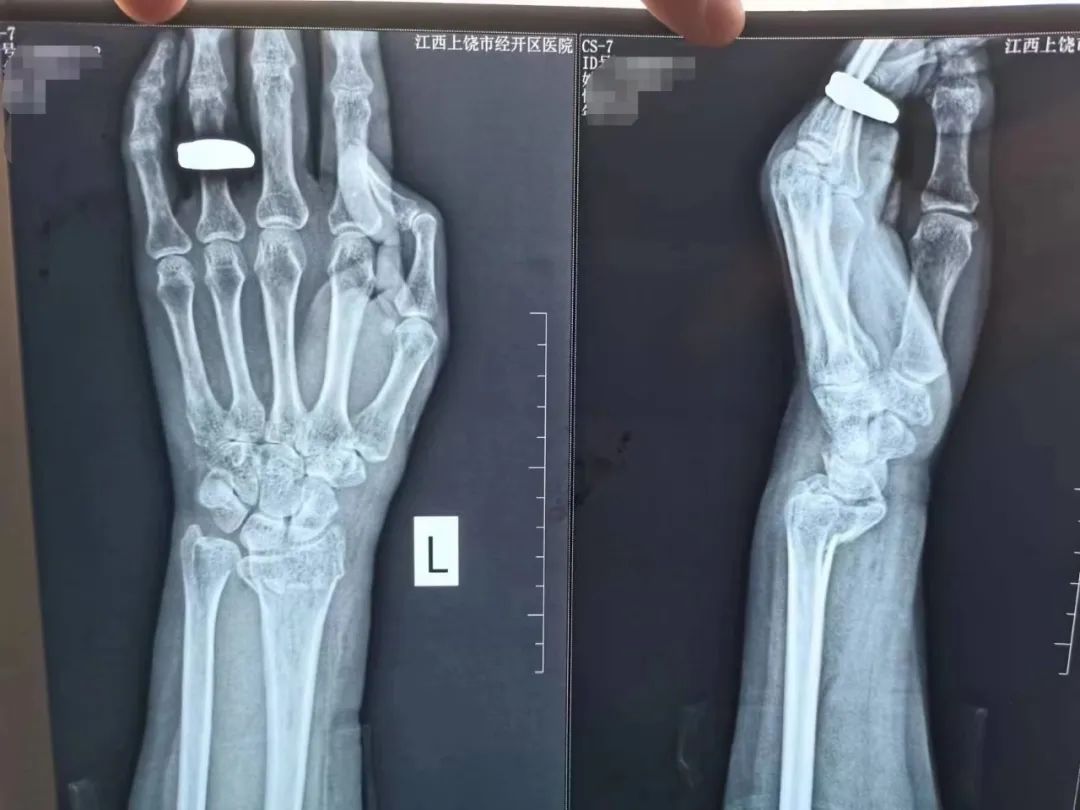

骨外科主任程广东医师亲自接诊,在仔细询问了顾奶奶的病史后,经CT及相关辅助检查诊断为“1.双侧桡骨远端骨折伴腕关节脱位 2.右侧第一掌骨骨折”。根据顾奶奶的病情及身体状况为顾奶奶量身制定手术方案,建议顾奶奶做两次手术来解决“双腕部骨折”问题。

手术后的第二天在经治医生的指导下顾奶奶就能进行患肢的功能锻炼,目前正在进一步康复中,此次的手术与治疗家属非常满意,连声称赞医务人员认真负责,服务细致,为表达对该院骨外科全体医护人员感激之情,顾奶奶和家属送来了锦旗。